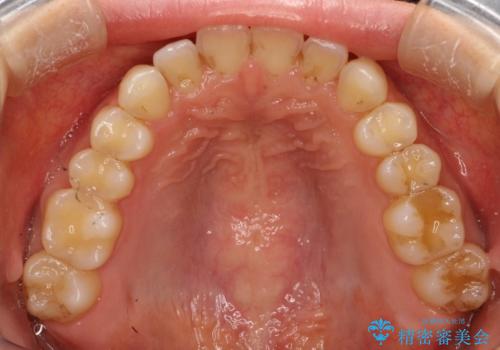

前歯のガタガタをインビザラインで目立たず矯正

- 目立たずに前歯を矯正したいとのことで来院されました。

歯と歯の間にわずかに隙間を作りスペースを確保し、インビザラインにて矯正を行うこととなりました。

前歯の微調整に少し時間がかかりましたが、整った歯並びにすることができました。